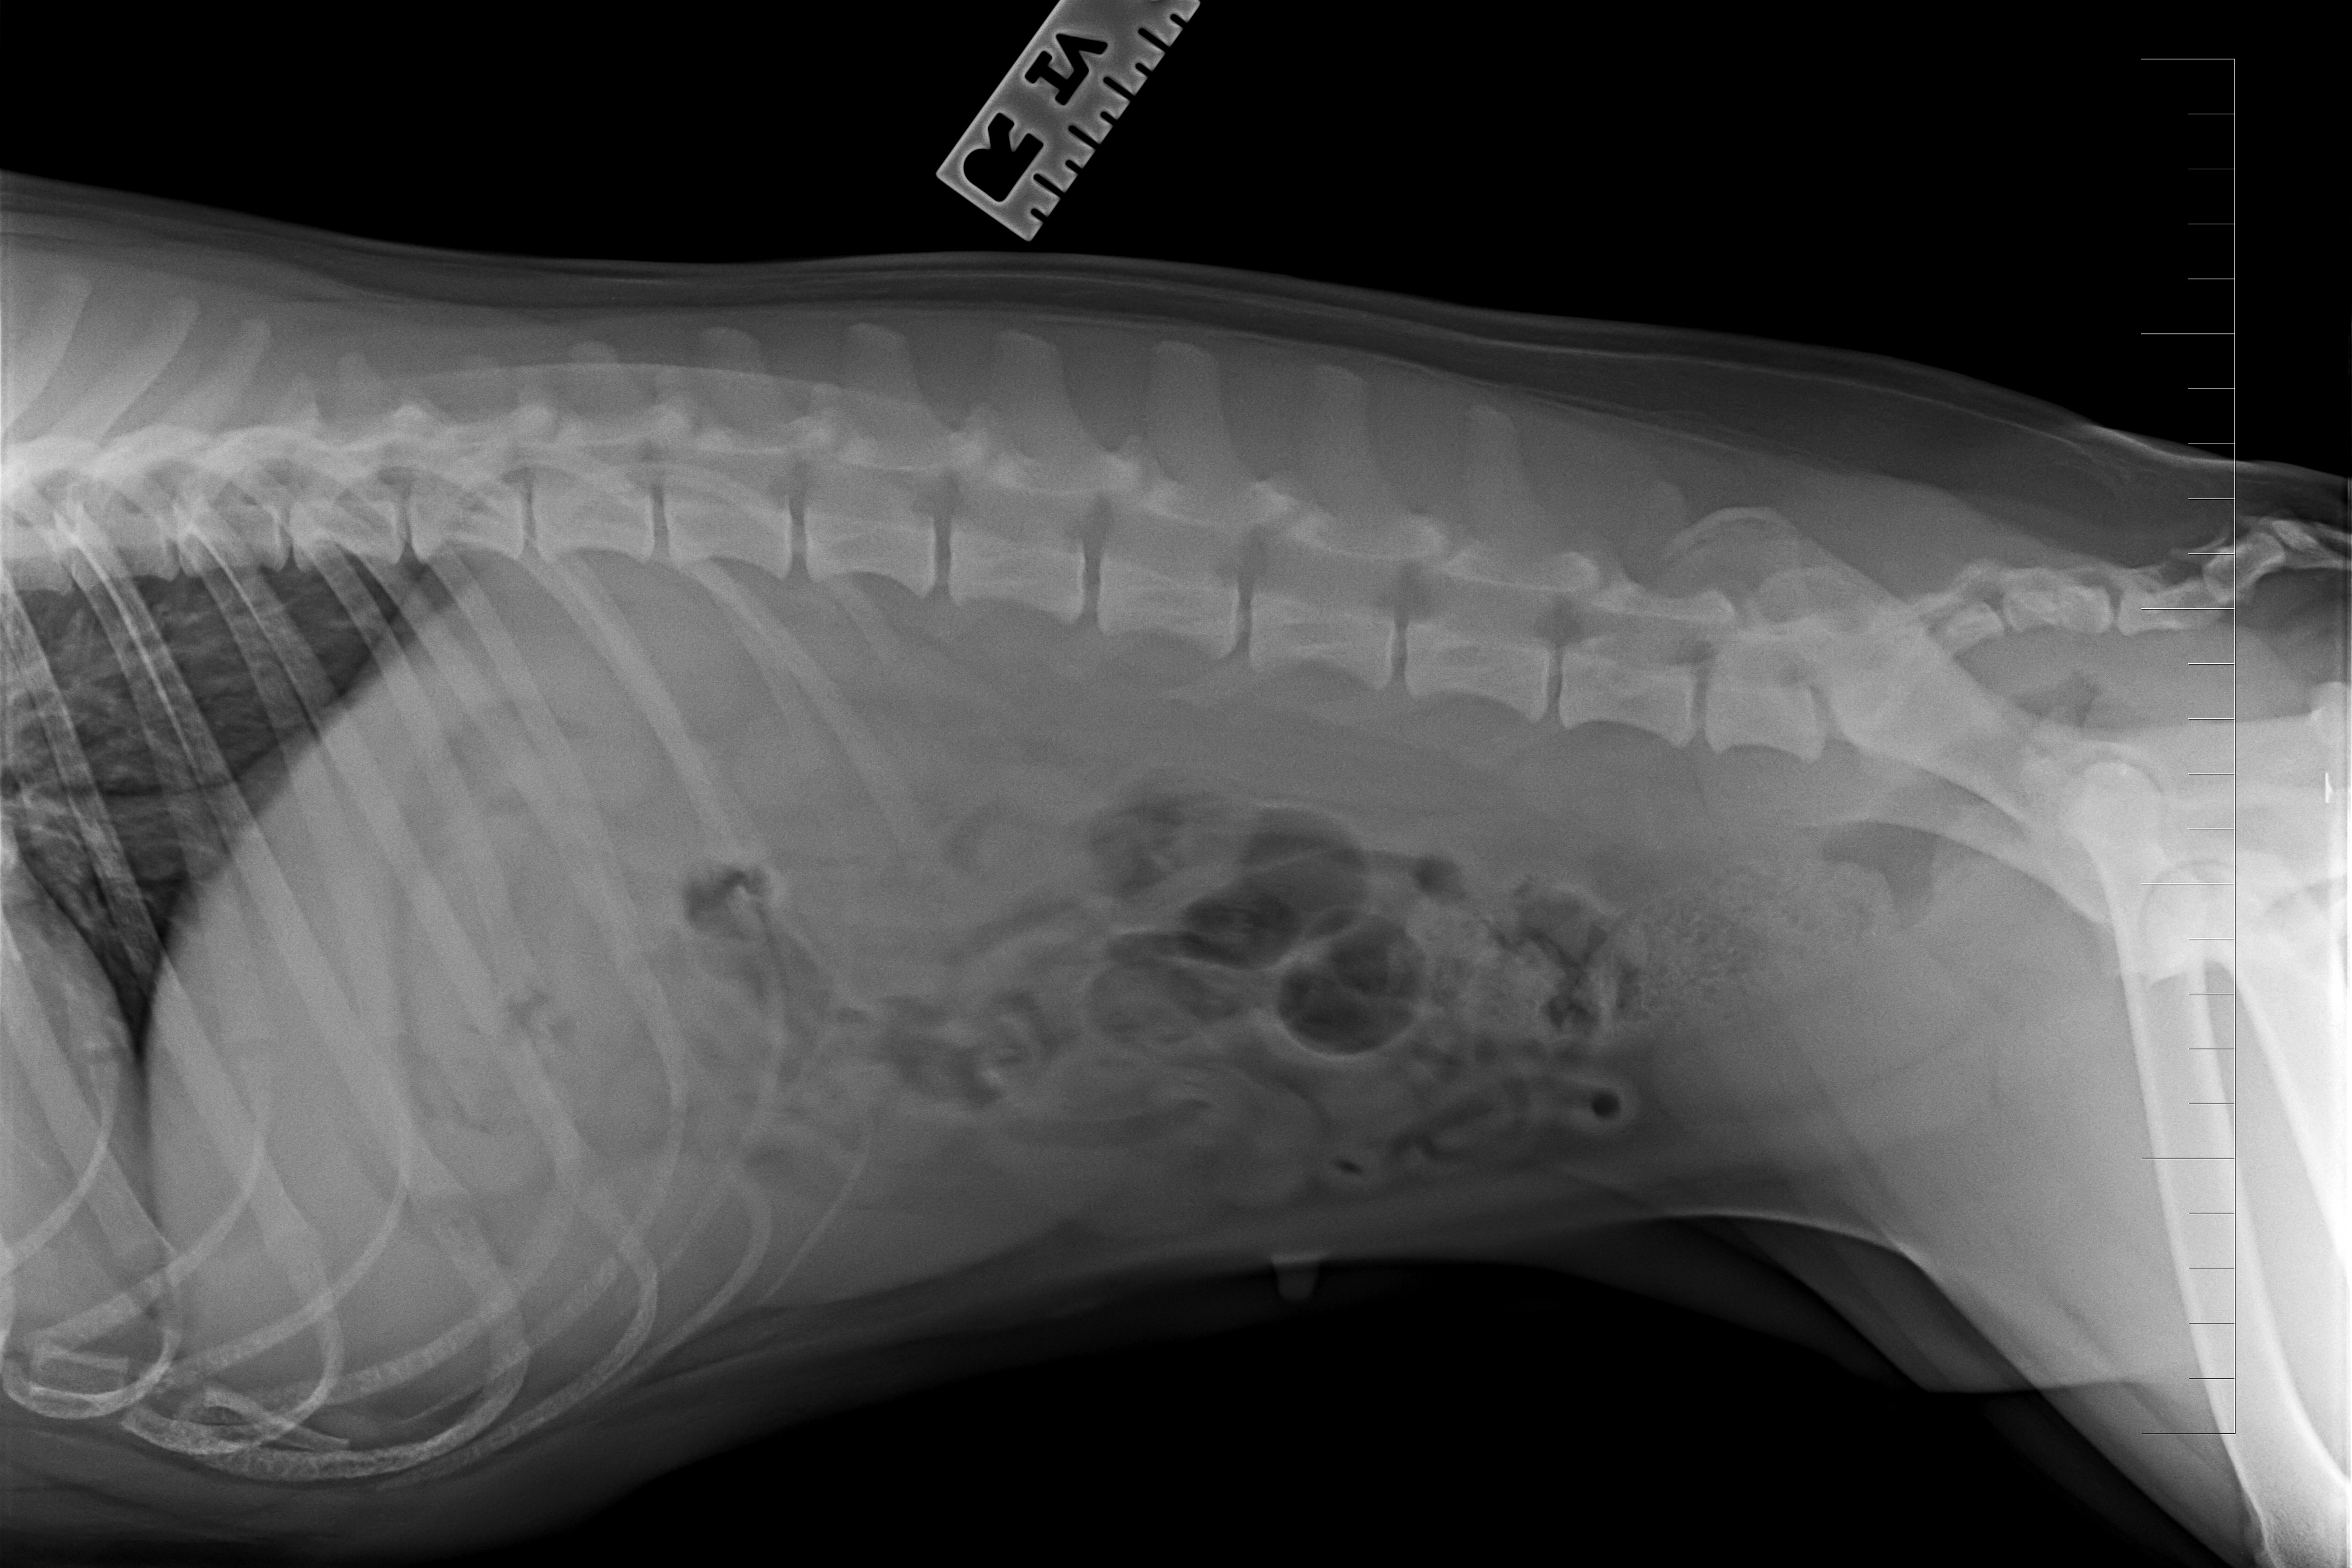

(5) 7 měsíců lat

(5) typ 3 páteř VD